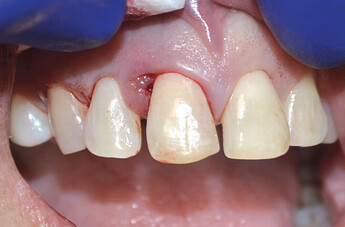

The patient presented with a failing tooth #8. After extraction, the socket shape resembled a triangle. Because of the round shape of the dental implant, there were gaps between the implant body and the alveolus which required grafting.